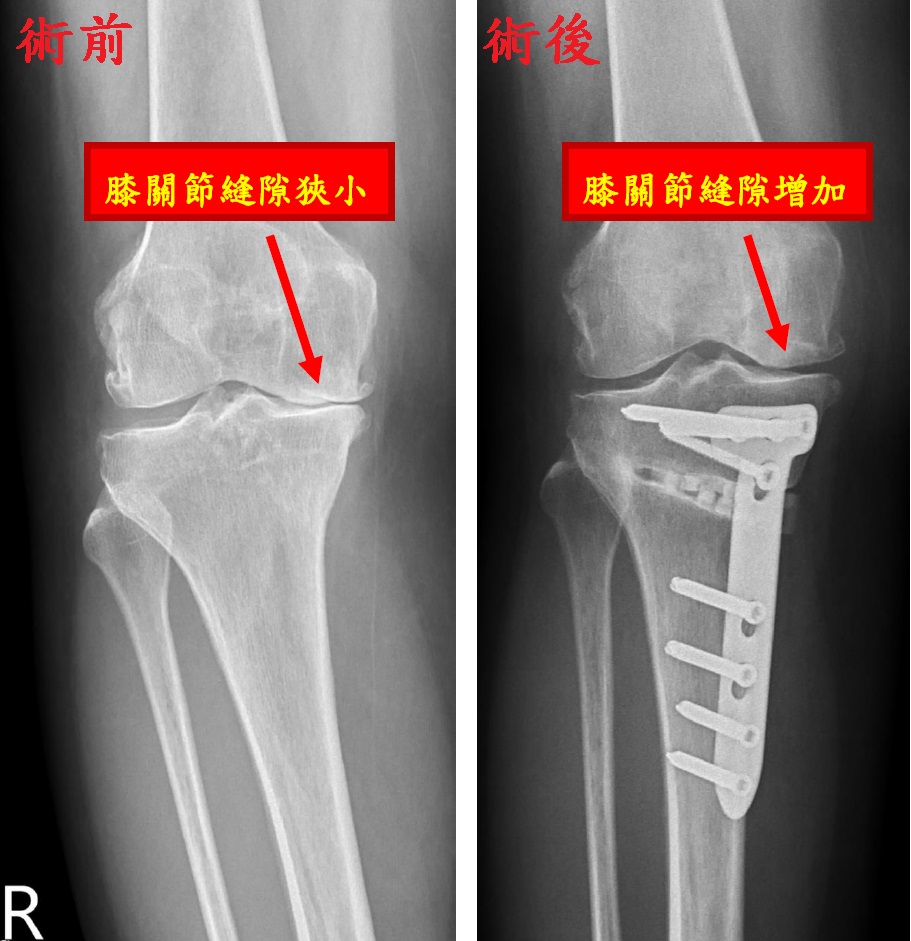

陳威仁醫師進一步說明,高位脛骨矯正手術前,需先拍攝整隻腳的X光片,並從髖關節中心到腳踝正中心畫一條線,這條線應穿過膝關節正中間。研究顯示,O型腿患者的關節退化風險比正常軸線患者高出4至5倍。手術前,將進行電腦斷層掃描,再利用3D列印技術設計手術模組,以精確計算需矯正的角度。手術過程中,通過3D列印模板,在脛骨(小腿骨)上進行精準切割,並用鋼板固定,從而將原本集中在膝內側的壓力分散至中間偏外的位置。這不僅能減輕疼痛,還能增加關節內側的縫隙,甚至可能促進軟骨再生,進而顯著延長膝關節的使用壽命。